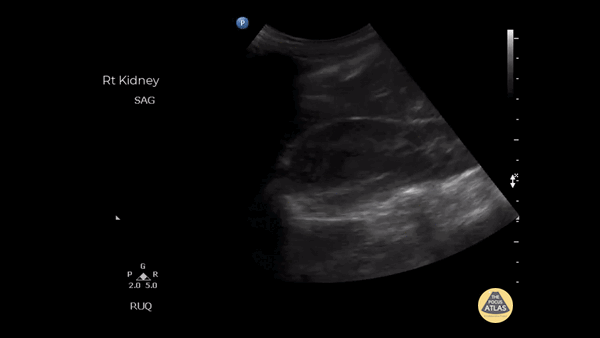

Renal/GU - Adrenal Metastasis

Patient presented with right flank pain and reported pain was similar to kidney stones. Large solid mass is observed and received a final diagnosis of adrenal metastasis after further imaging. Image courtesy of Robert Jones DO, FACEP @RJonesSonoEM Director, Emergency Ultrasound; MetroHealth Medical Center; Professor, Case Western Reserve Medical School, Cleveland, OH View his original post here